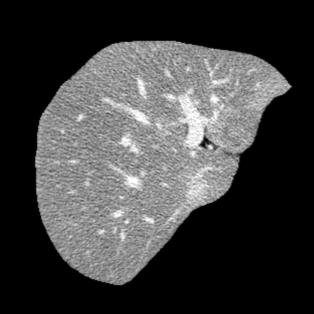

Manually segmenting the hepatic vessels from Computer Tomography (CT) is far more expertise-demanding and laborious than other structures due to the low-contrast and complex morphology of vessels, resulting in the extreme lack of high-quality labeled data. Without sufficient high-quality annotations, the usual data-driven learning-based approaches struggle with deficient training. On the other hand, directly introducing additional data with low-quality annotations may confuse the network, leading to undesirable performance degradation. To address this issue, we propose a novel mean-teacher-assisted confident learning framework to robustly exploit the noisy labeled data for the challenging hepatic vessel segmentation task. Specifically, with the adapted confident learning assisted by a third party, i.e., the weight-averaged teacher model, the noisy labels in the additional low-quality dataset can be transformed from "encumbrance" to "treasure" via progressive pixel-wise soft-correction, thus providing productive guidance. Extensive experiments using two public datasets demonstrate the superiority of the proposed framework as well as the effectiveness of each component.